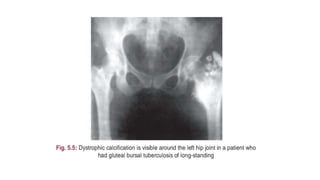

• X-ray of the affected part-in antero-posterior and lateral views and

x-ray of the chest are mandatory.

• In active disease -localized osteoporosis is the first radiological sign .

• The articular margins and bony cortices become hazy(giving‘’washed

out”) appearance and there is development of areas of trabecular or

bony destruction and osteolysis.

• Diminution of joint space in x-rays in area of articular cartilage